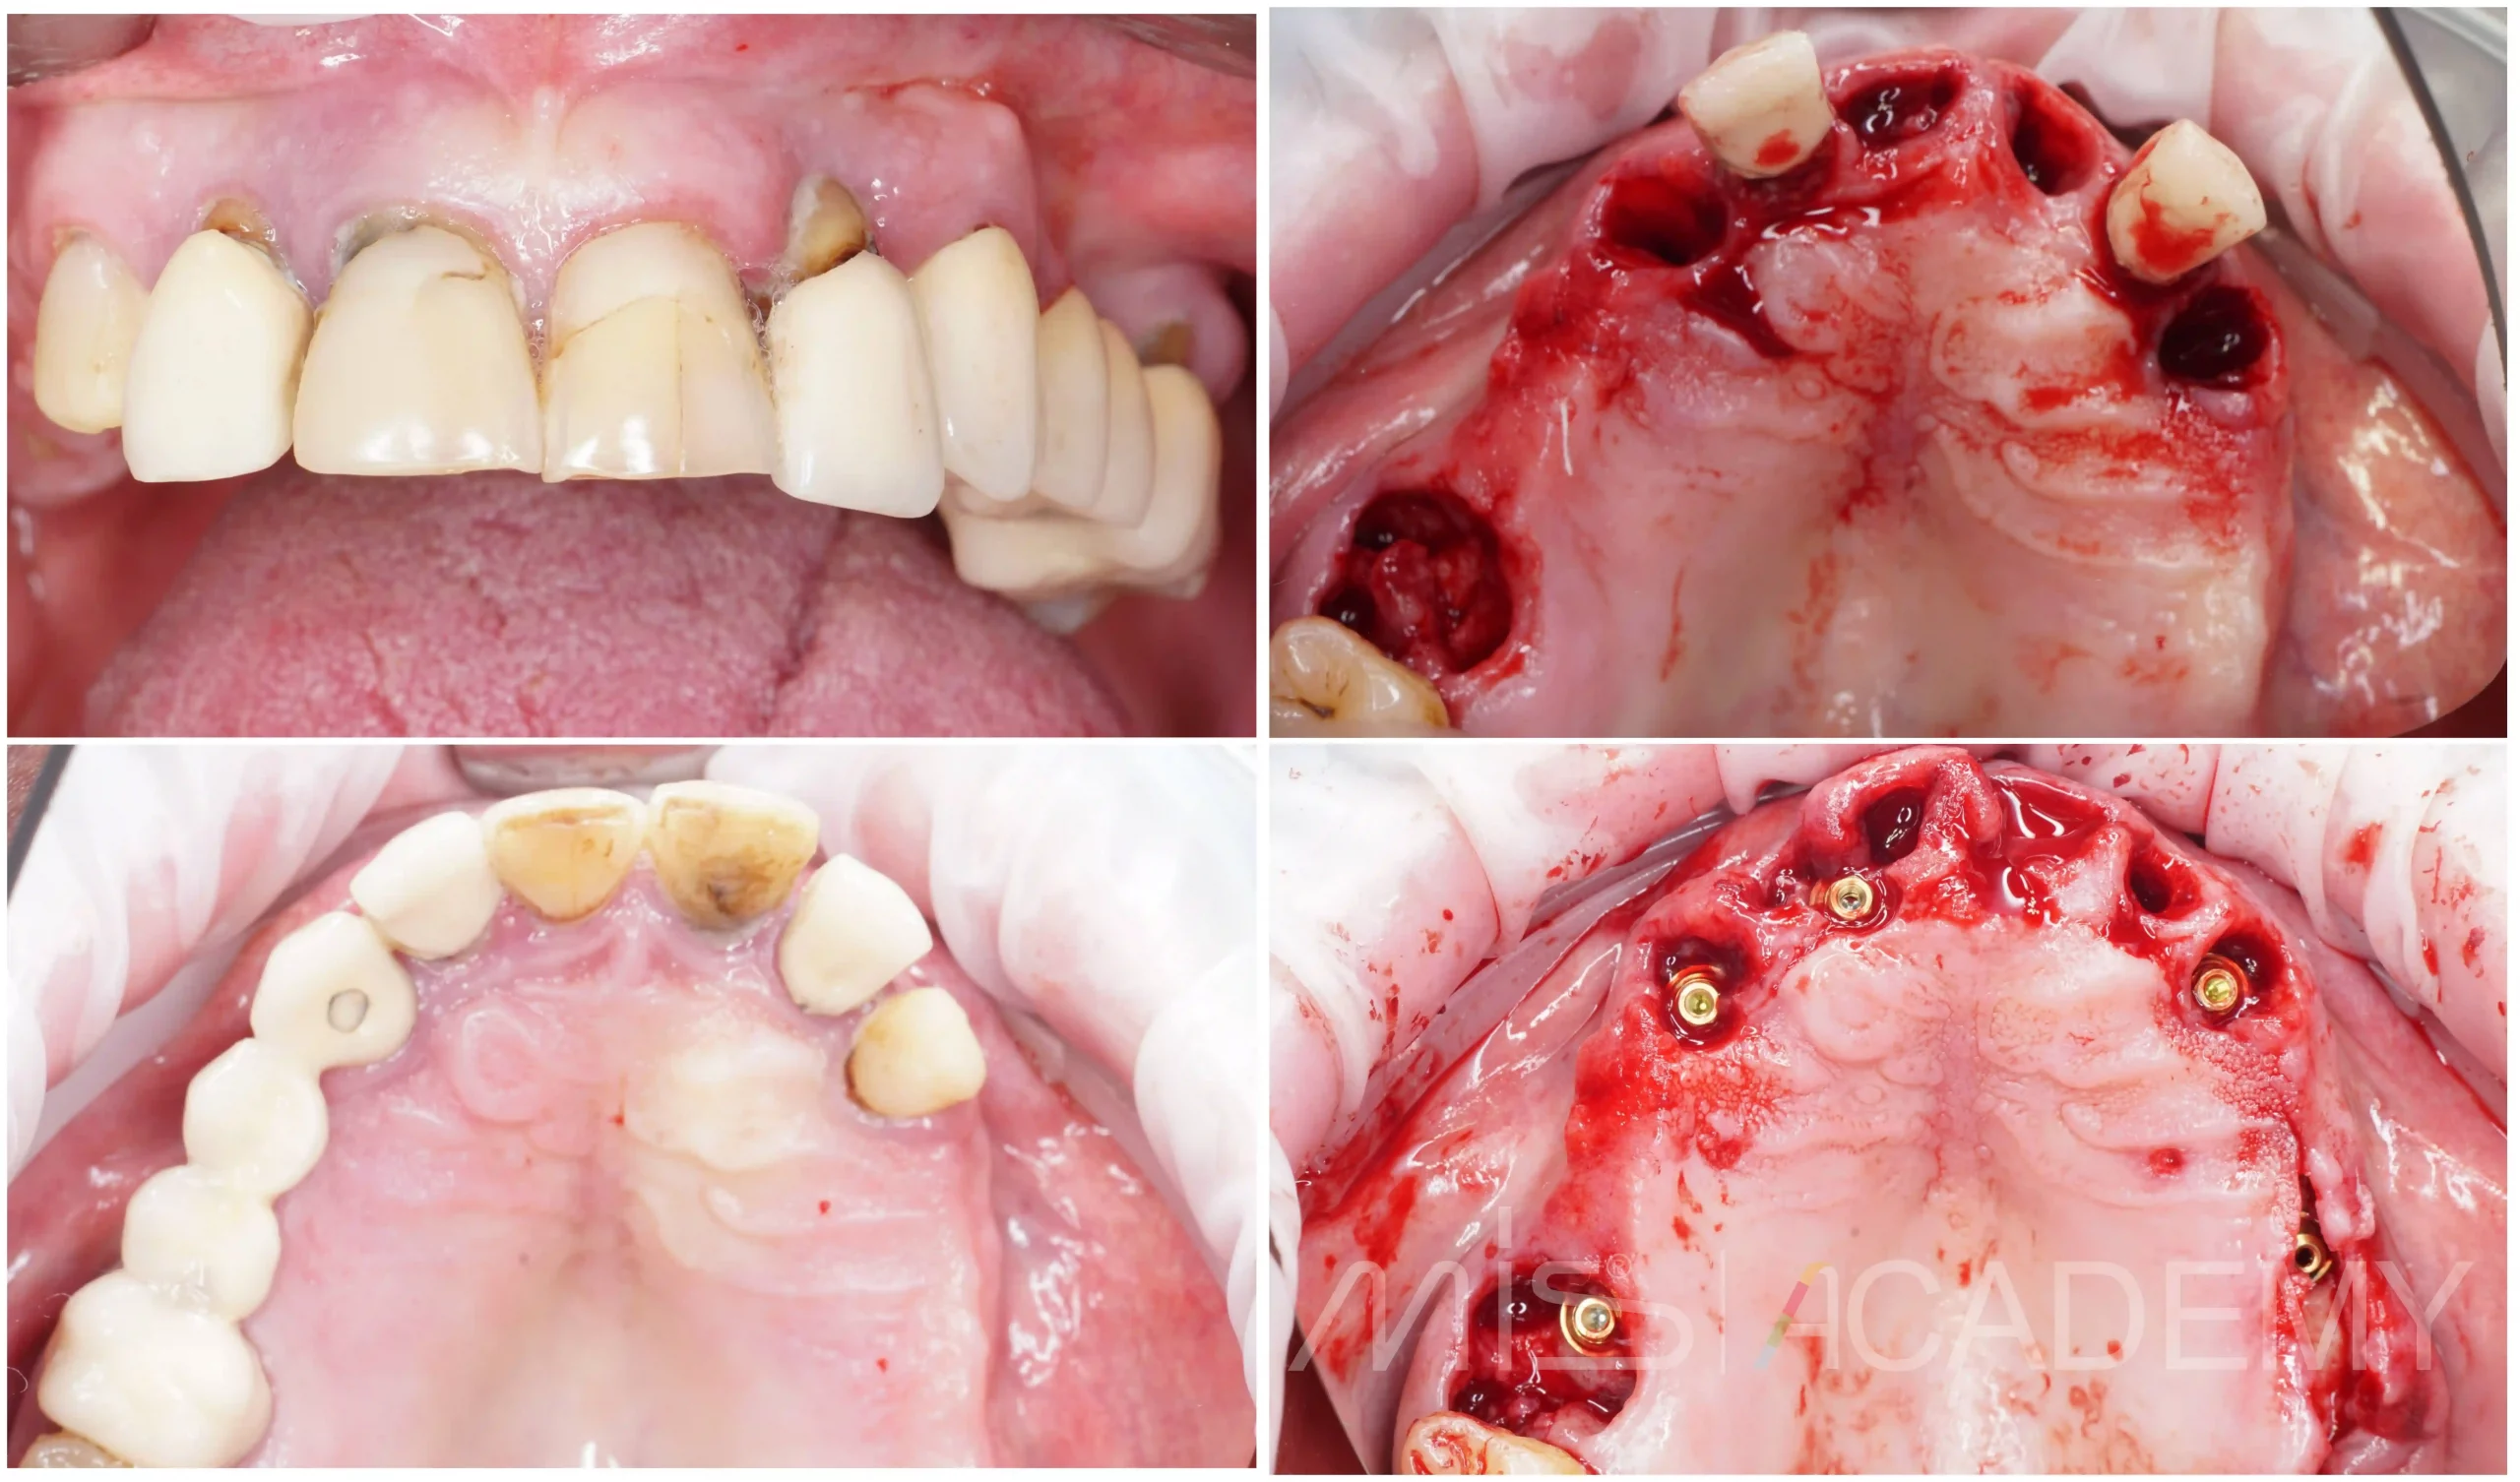

Реферативный пациент, на момент обращения 74 года. Курит до 2 пачек в день. Выраженные проблемы на обеих челюстях: подвижность зубов, хроническое воспаление практически в каждой зоне. В таких ситуациях мы не идём в одномоментную двухчелюстную реабилитацию. Выбрана поэтапная тактика с интервалом 1,5–2 месяца-более безопасно и предсказуемо для пациента с высоким риском.

Первый этап — верхняя челюсть: удаление несостоятельных зубов, установка имплантатов MIS C1, протезирование на мультиюнитах.

Через 2 месяца — нижняя челюсть: удаление зубов, имплантаты MIS C1, протезирование с уровня коннект абатментов.